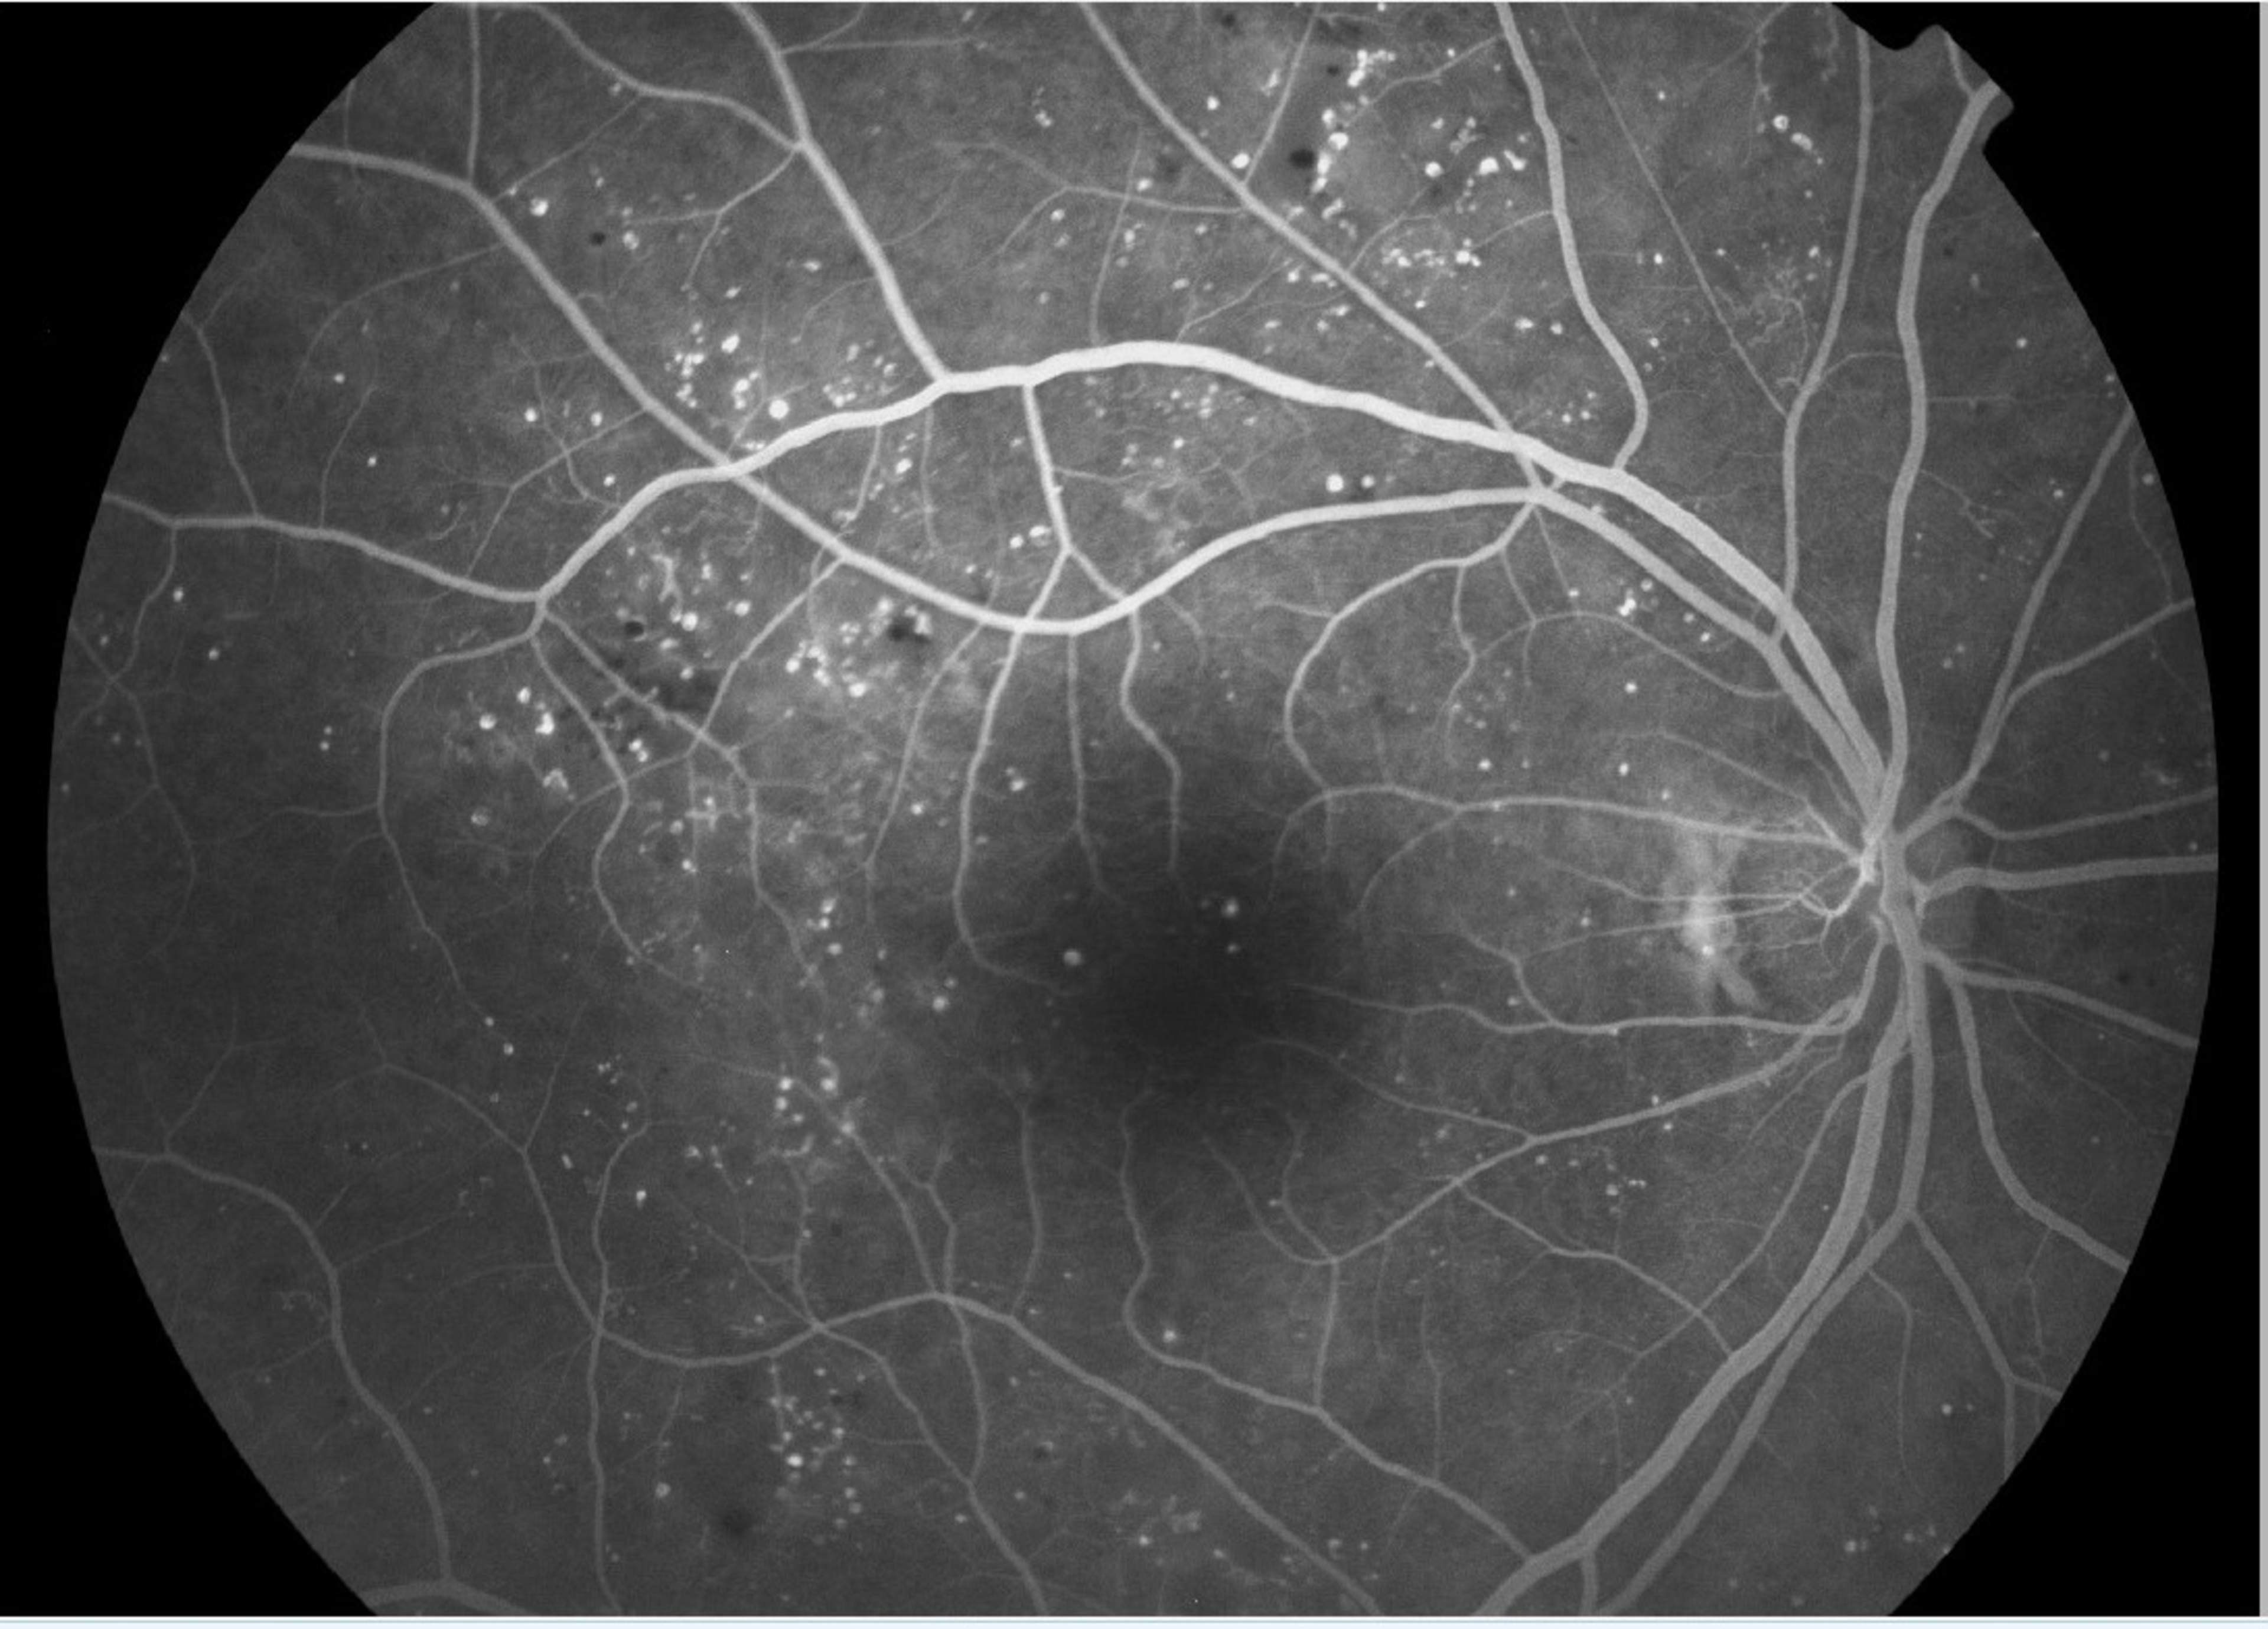

Vid kontrastfotografering av ögat (FAG, dvs. fluoresceinangiografi och ICG, dvs. indocyaninangiografi) undersöks blodkärlens uppbyggnad och funktion. Vid kontrastfotografering injiceras via en kanyl i patientens arm färgämne i blodkärlen. Blodcirkulationen transporterar färgmedlet även ut i små blodkärl som inte nödvändigtvis syns i en klinisk undersökning. Vid undersökningen tas det en stor mängd bilder av ögonbottnen.